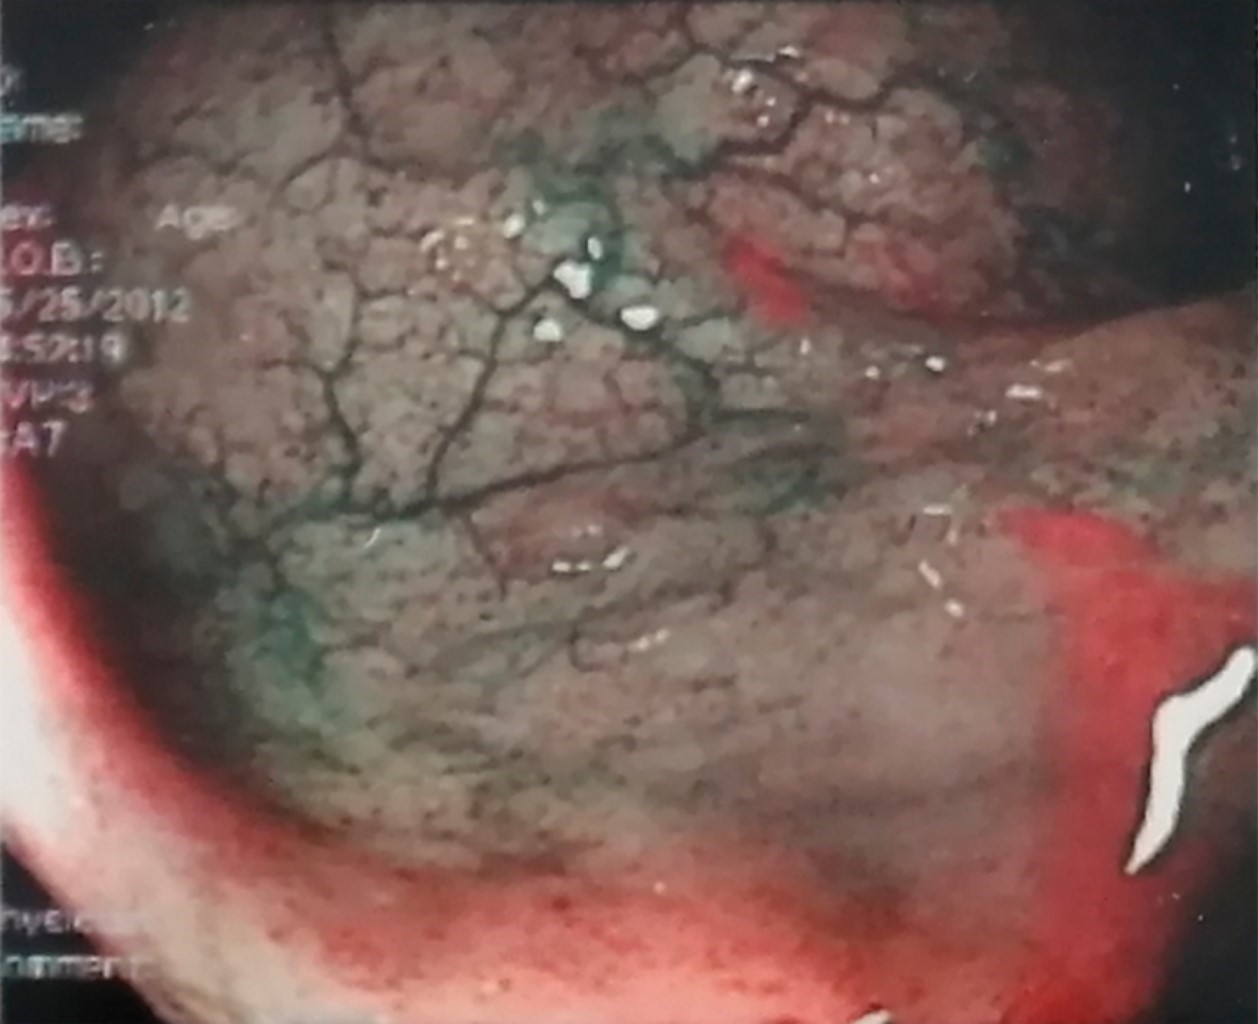

Paciente femenino de 25 años de edad, originaria y residente de Hermosillo, Sonora, México. Inició padecimiento desde el nacimiento con infecciones respiratorias recurrentes en número mayor de ocho en un año, sin presentar infecciones respiratorias graves. Se estudió por diarrea crónica sin etiología definida por gastroenterología, en mayo de 2012 se agudizó la sintomatología al presentar evacuaciones disminuidas en consistencia hasta en 15 eventos al día, dolor epigástrico y rectorragia. Gastroenterología descartó enfermedad celíaca. Inmunología realizó estudios complementarios donde se reportó hipogammaglobulinemia (Tabla 1). Se diagnosticó IDCV e inició el tratamiento con inmunoglobulina intravenosa (400-600 mg/kg) cada cuatro semanas con mejoría clínica completa. Los resultados de la secuenciación de ADN de siguiente generación (NGS) identificaron una variante en TNFRSF13B en el exón 3 c.310T>C; p.cys104Arg. Variante heterocigota clasificada como patogénica y con tipo de herencia autosómica dominante. Actualmente la paciente continúa con aplicación de inmunoglobulina intravenosa en su lugar de residencia, acude a valoración de forma semestral.

El tratamiento amerita la administración de inmunoglobulina intravenosa cada tres a cuatro semanas a dosis de 400-600 mg/kg, con el cual hay mejoría clínica.5 Los hallazgos de la colonoscopia mostraron hiperplasia nodular linfoide, que no se reporta con frecuencia como hallazgo en esta enfermedad. Los cambios en la mucosa del colon se ilustran en las Figuras 1 y 2.